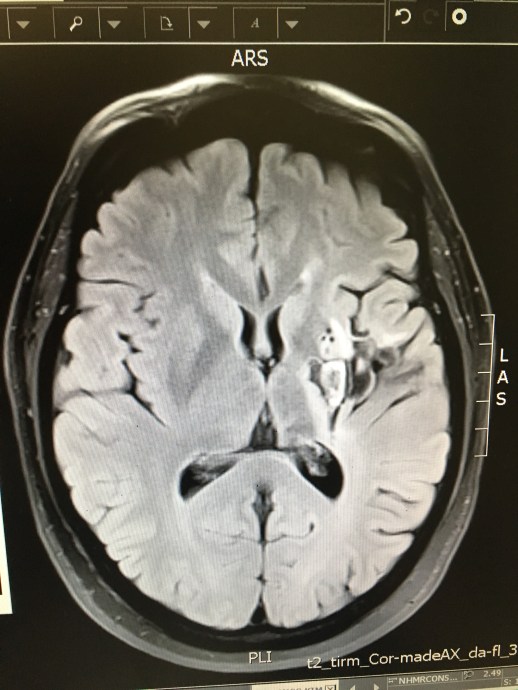

This is a picture of my brain, you can see the damaged area half way up and slightly to the right, with the stem cell insertion holes just above it shown as three black dots.